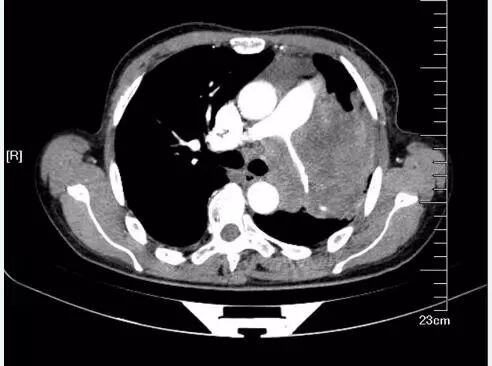

肿块包绕肺动脉干,肺动脉干变细,纵隔、肺门可见明显肿大淋巴结,相互融合,与肺门肿块分界不清,形成“冰冻纵隔”,这种贪得无厌的肿瘤,几乎都是小细胞肺癌。假如病理科报道:鳞癌。你可以要求病理科做免疫组化,再看看片子,不要冲动

纵隔、肺门可见明显肿大淋巴结,相互融合,与肺门肿块分界不清,形成“冰冻纵隔”,几乎都是可恶的小细胞肺癌。